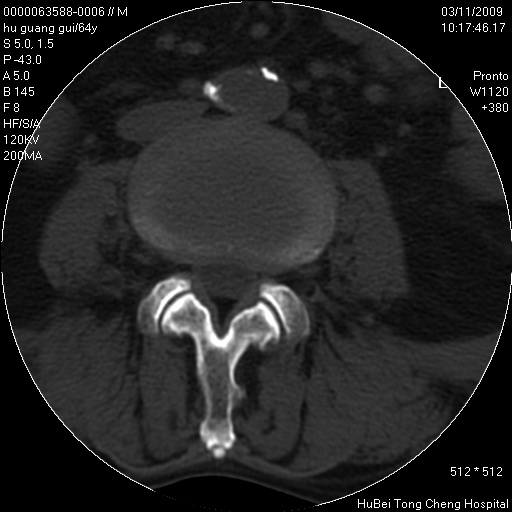

患者 男,64岁。腰痛十余天。(临床未提供其他病史)

临床诊断:腰痛原因待查(腰椎间盘突出症?)。

腰椎间盘ct轴位平扫(层厚5mm,层距4mm),图像如下:

腰椎退行性变,腰4—5椎间盘膨出。

右侧骶骨侧块骨侵蚀,骶髂关节骨性关节面破坏,并见软组织肿块,考虑骨转移瘤可能,进一步检查。

1.腰椎退行性变,腰4—5椎间盘膨出。

2.右侧骶骨侧块骨侵蚀,骶髂关节骨性关节面破坏,并见软组织肿块,考虑:脊索瘤,骨转移瘤可能,进一步检查。

1)腰椎退行性变,l4—5椎间盘膨出。2)骶骨右侧块骨转移瘤可能,3)水平骶椎。建议作一步检查。